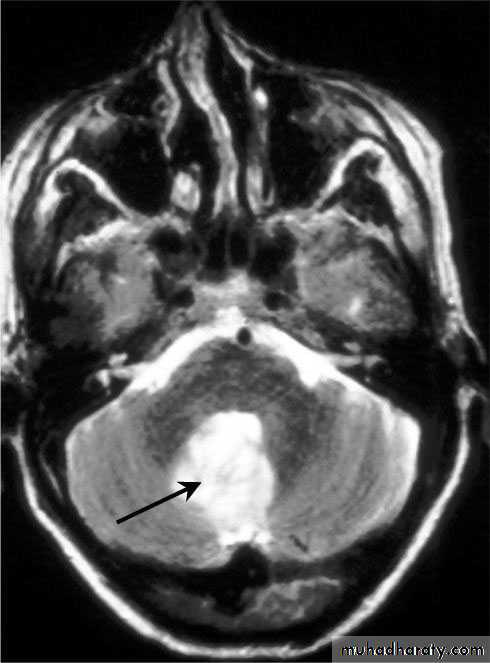

Cerebellar Abscess